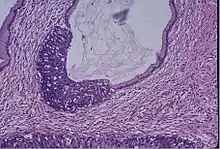

Cervical cancer

Cervical screening by the Pap test or other methods is highly effective at detecting and preventing cervical cancer, although there is a serious risk of overtreatment in young women up to the age of 20 or beyond, who are prone to have many abnormal cells which clear up naturally.[24] There is a considerable range in the recommended age at which to begin screening around the world. According to the 2010 European guidelines for cervical cancer screening, the age at which to commence screening ranges between 20–30 years of age, "but preferentially not before age 25 or 30 years", depending on the burden of the disease in the population and the available resources.[25]